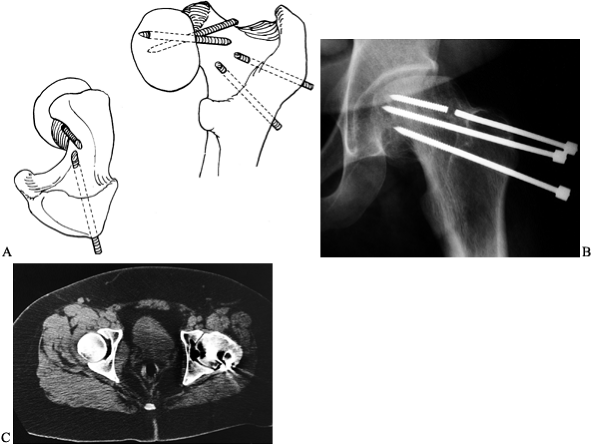

Figure 172.14. A: AP radiograph of the pelvis of a 13-year-old girl, 13 months after in situ

fixation of a left SCFE. The radiographs with the fixation present were not available, and the single screw had since been removed. B: CT scan demonstrates the old screw track (arrow), with the tip being extremely close to the cartilage surface (arrowhead). The hip was painful and in an unacceptable position due to a marked flexion contracture. Conservative therapy was not beneficial and an arthrodesis was performed at age 14 years. C: Last follow-up at age 16 years demonstrated no pain, excellent ambulation ability, and a solid arthrodesis. |

Unlike AVN, chondrolysis can occur in the untreated stable SCFE. It may

be aggravated by persistent intraarticular fixation or with spica

casts. In the past, it was thought that black children and those of

Hawaiian ancestry were more susceptible to its development (58,85); recent reports question this view (4,40,80).

The exact etiology is unknown, although it may be an autoimmune process

aggravated by the persistent pin penetration and secondary mechanical

joint damage (63). Chondrolysis does not occur

in all joints with pin penetration; however, its incidence is higher as

the number of pins increases or they become closer to the subchondral

bone (10). Transient intraoperative pin penetration that is corrected at surgery does not increase the risk of chondrolysis (96).

diagnosis of the SCFE. Its clinical hallmark is severe loss of motion

and pain in relation to slip magnitude. It is radiographically defined

as a loss of more than 50% of the width of the weight-bearing portion

of the articular space in children with unilateral SCFE (Fig. 172.14),

or less than 3 mm width of the articular space in children with

bilateral SCFE. When the diagnosis is suspected but there is no plain

radiographic evidence, a technetium-99 methylene-diphosphonate bone

scan may be helpful (57). Marked periarticular

uptake and premature closure of the greater trochanteric physis are

highly predictive of future chondrolysis.